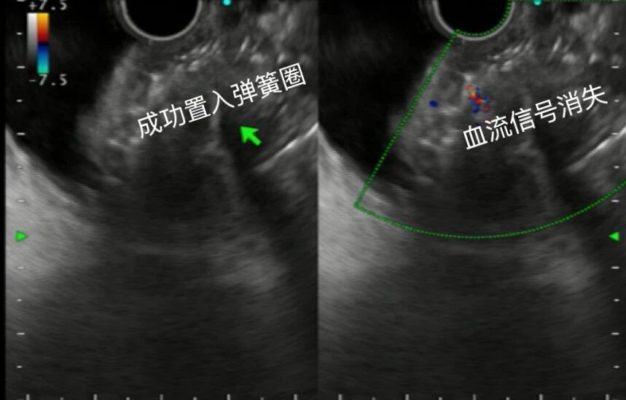

随后孔灿灿向已部分栓塞的血管内注入适量组织黏合剂,使其与弹簧圈紧密结合,形成稳固的复合栓塞体,彻底封堵异常曲张血管,阻断出血风险。手术过程顺利,术后内镜下可见静脉曲张变硬,血流信号消失。两天后,陈先生顺利出院,后续待曲张静脉自行慢慢恢复,定期复查即可。

内镜超声引导下成功置入弹簧圈,血流信号消失